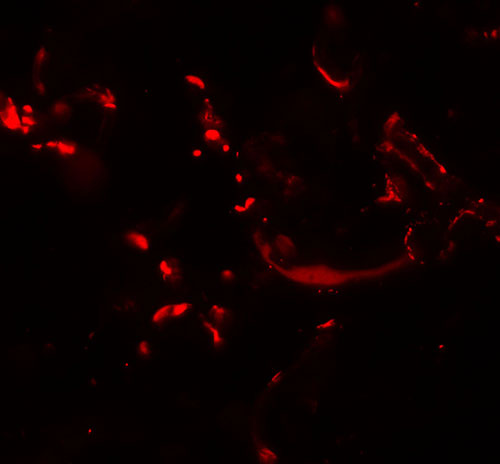

Immunofluorescence of HHATL in human skin tissue with HHATL antibody at 20 μg/mL. |